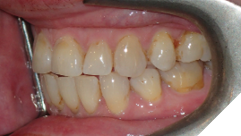

The majority of the orthodontic practices offer a period of “supervised retention” to their patients and communicates the customized retention recommendation with the patient’s general dentists. It is extremely important to work as a team to achieve long term clinical success in maintaining a functional bite and aesthetic smile. The general dentists continue to see their patients on a regular basis and have an opportunity to assess the orthodontic retainers and the bite after the supervised retention period is completed by the orthodontists. With great care, orthodontic retainers would serve for a long time (Fig. 1) without any major issues. However, in some cases, the failure to notice the clinical problems early on results in functional issues that would require a comprehensive orthodontic treatment to correct it (Fig. 2).

Fig. 2A

Fig. 2B

Fig. 2C